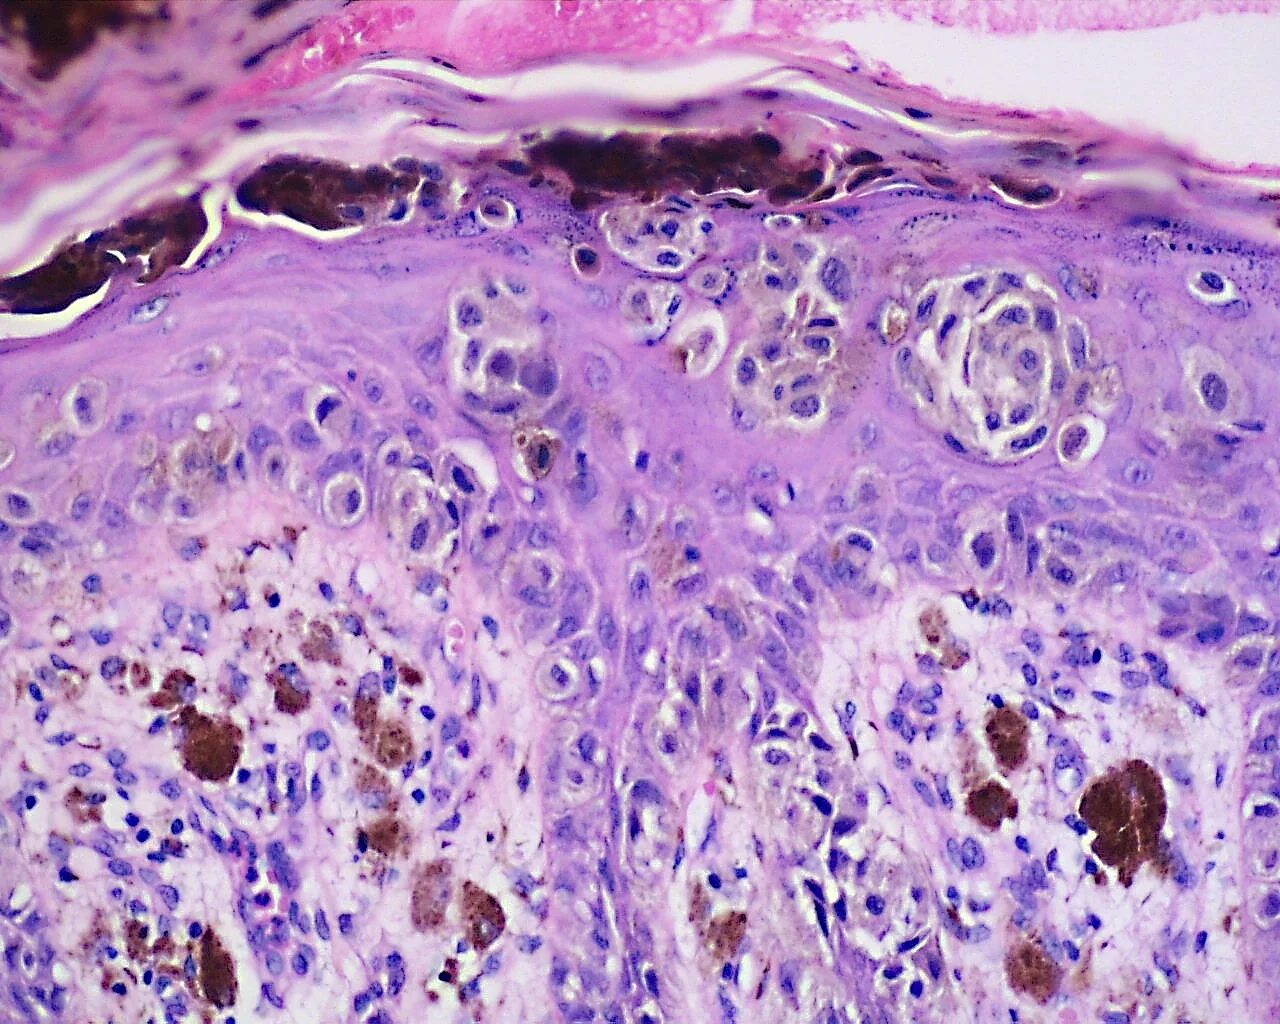

Гистология фото